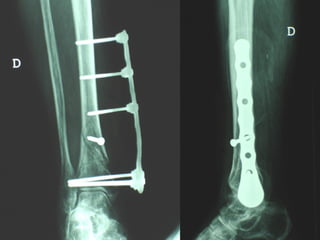

Dal Gennaio 2000 al Febbraio 2006 abbiamo trattato 167 fratture chiuse  con placca percutanea  in 164 pazienti :  27 lesioni diafisarie di gamba, 12 piloni tibiali ,  11 fratture prossimali di tibia, 36 fratture sovracondiloidee di femore, 17 fratture diafisarie di femore, 43 fratture metaepifisarie prossimali di omero, 21 diafisarie d’omero.  156 guarigioni 8 fallimenti

Dal Giugno 2002 al Dicembre 2004 abbiamo trattato 5 fratture esposte: 3 di tibia e 2 di ulna 5 guarigioni

I buoni risultati ottenuti dipendono da 5 punti fondamentali:   una accurata riduzione percutanea della frattura  precise vie di accesso  l’utilizzo della placca che consenta il più lungo braccio di leva possibile il pretensionamento della placca  una sintesi con un ridotto numero di viti

VANTAGGI CHIRURGIA MININVASIVA Mini Open Inserimento della placca sottocutaneo per scivolamento Viti percutanee Preservazione dei tessuti molli Ridotto danno vascolare Rapida ripresa funzionale